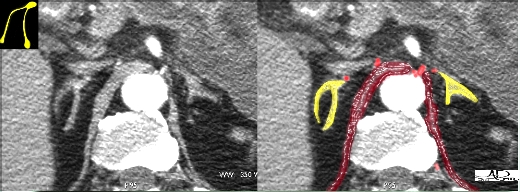

| This coronal T1-weighted image has been overlayed with the arterial anatomy of the adrenal. Each gland receives arterial blood from three arteries – the superior, middle and inferior adrenal arteries.

Courtesy of: Ashley Davidoff, M.D.adrenals-0006 |

In this early phase arterial CT, multiple branches of the adrenal arteries are overlayed in red. Branches of the inferior phrenic arteries are seen in close association with the crura of the diaphragm. The veins have not yet filled with contrast.Courtesy of: Ashley Davidoff, M.D. |